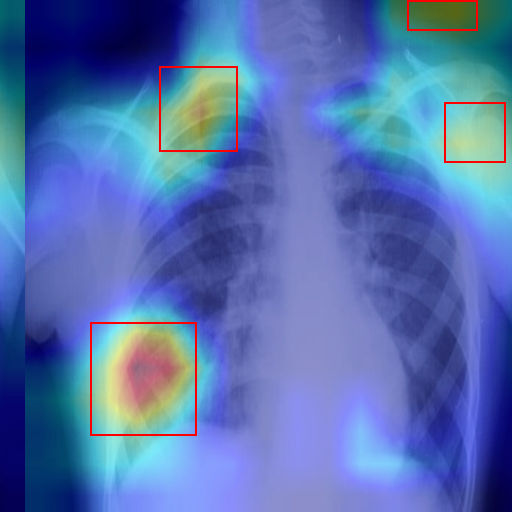

Thoracic X-Ray

Max • Dog

2024-02-14

Cardiomegaly (91.4%) Completed